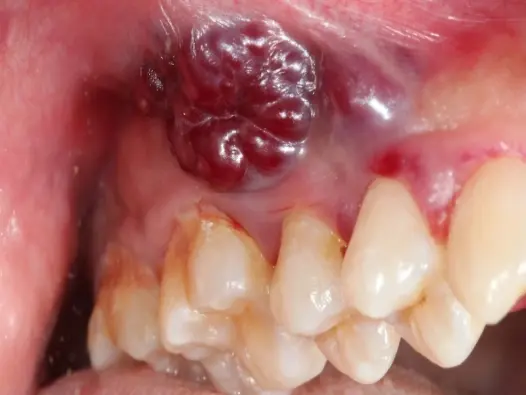

Hình ảnh bệnh lao hạch - Cách phân biệt với các loại u hạch

Xem các hình ảnh bệnh lao hạch để nhận biết dấu hiệu sớm. Bài viết cung cấp thông tin y khoa về triệu chứng, nguyên nhân và các phương pháp điều trị hiệu quả.